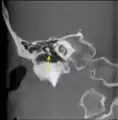

Scanner en coupe coronale montrant un malleus